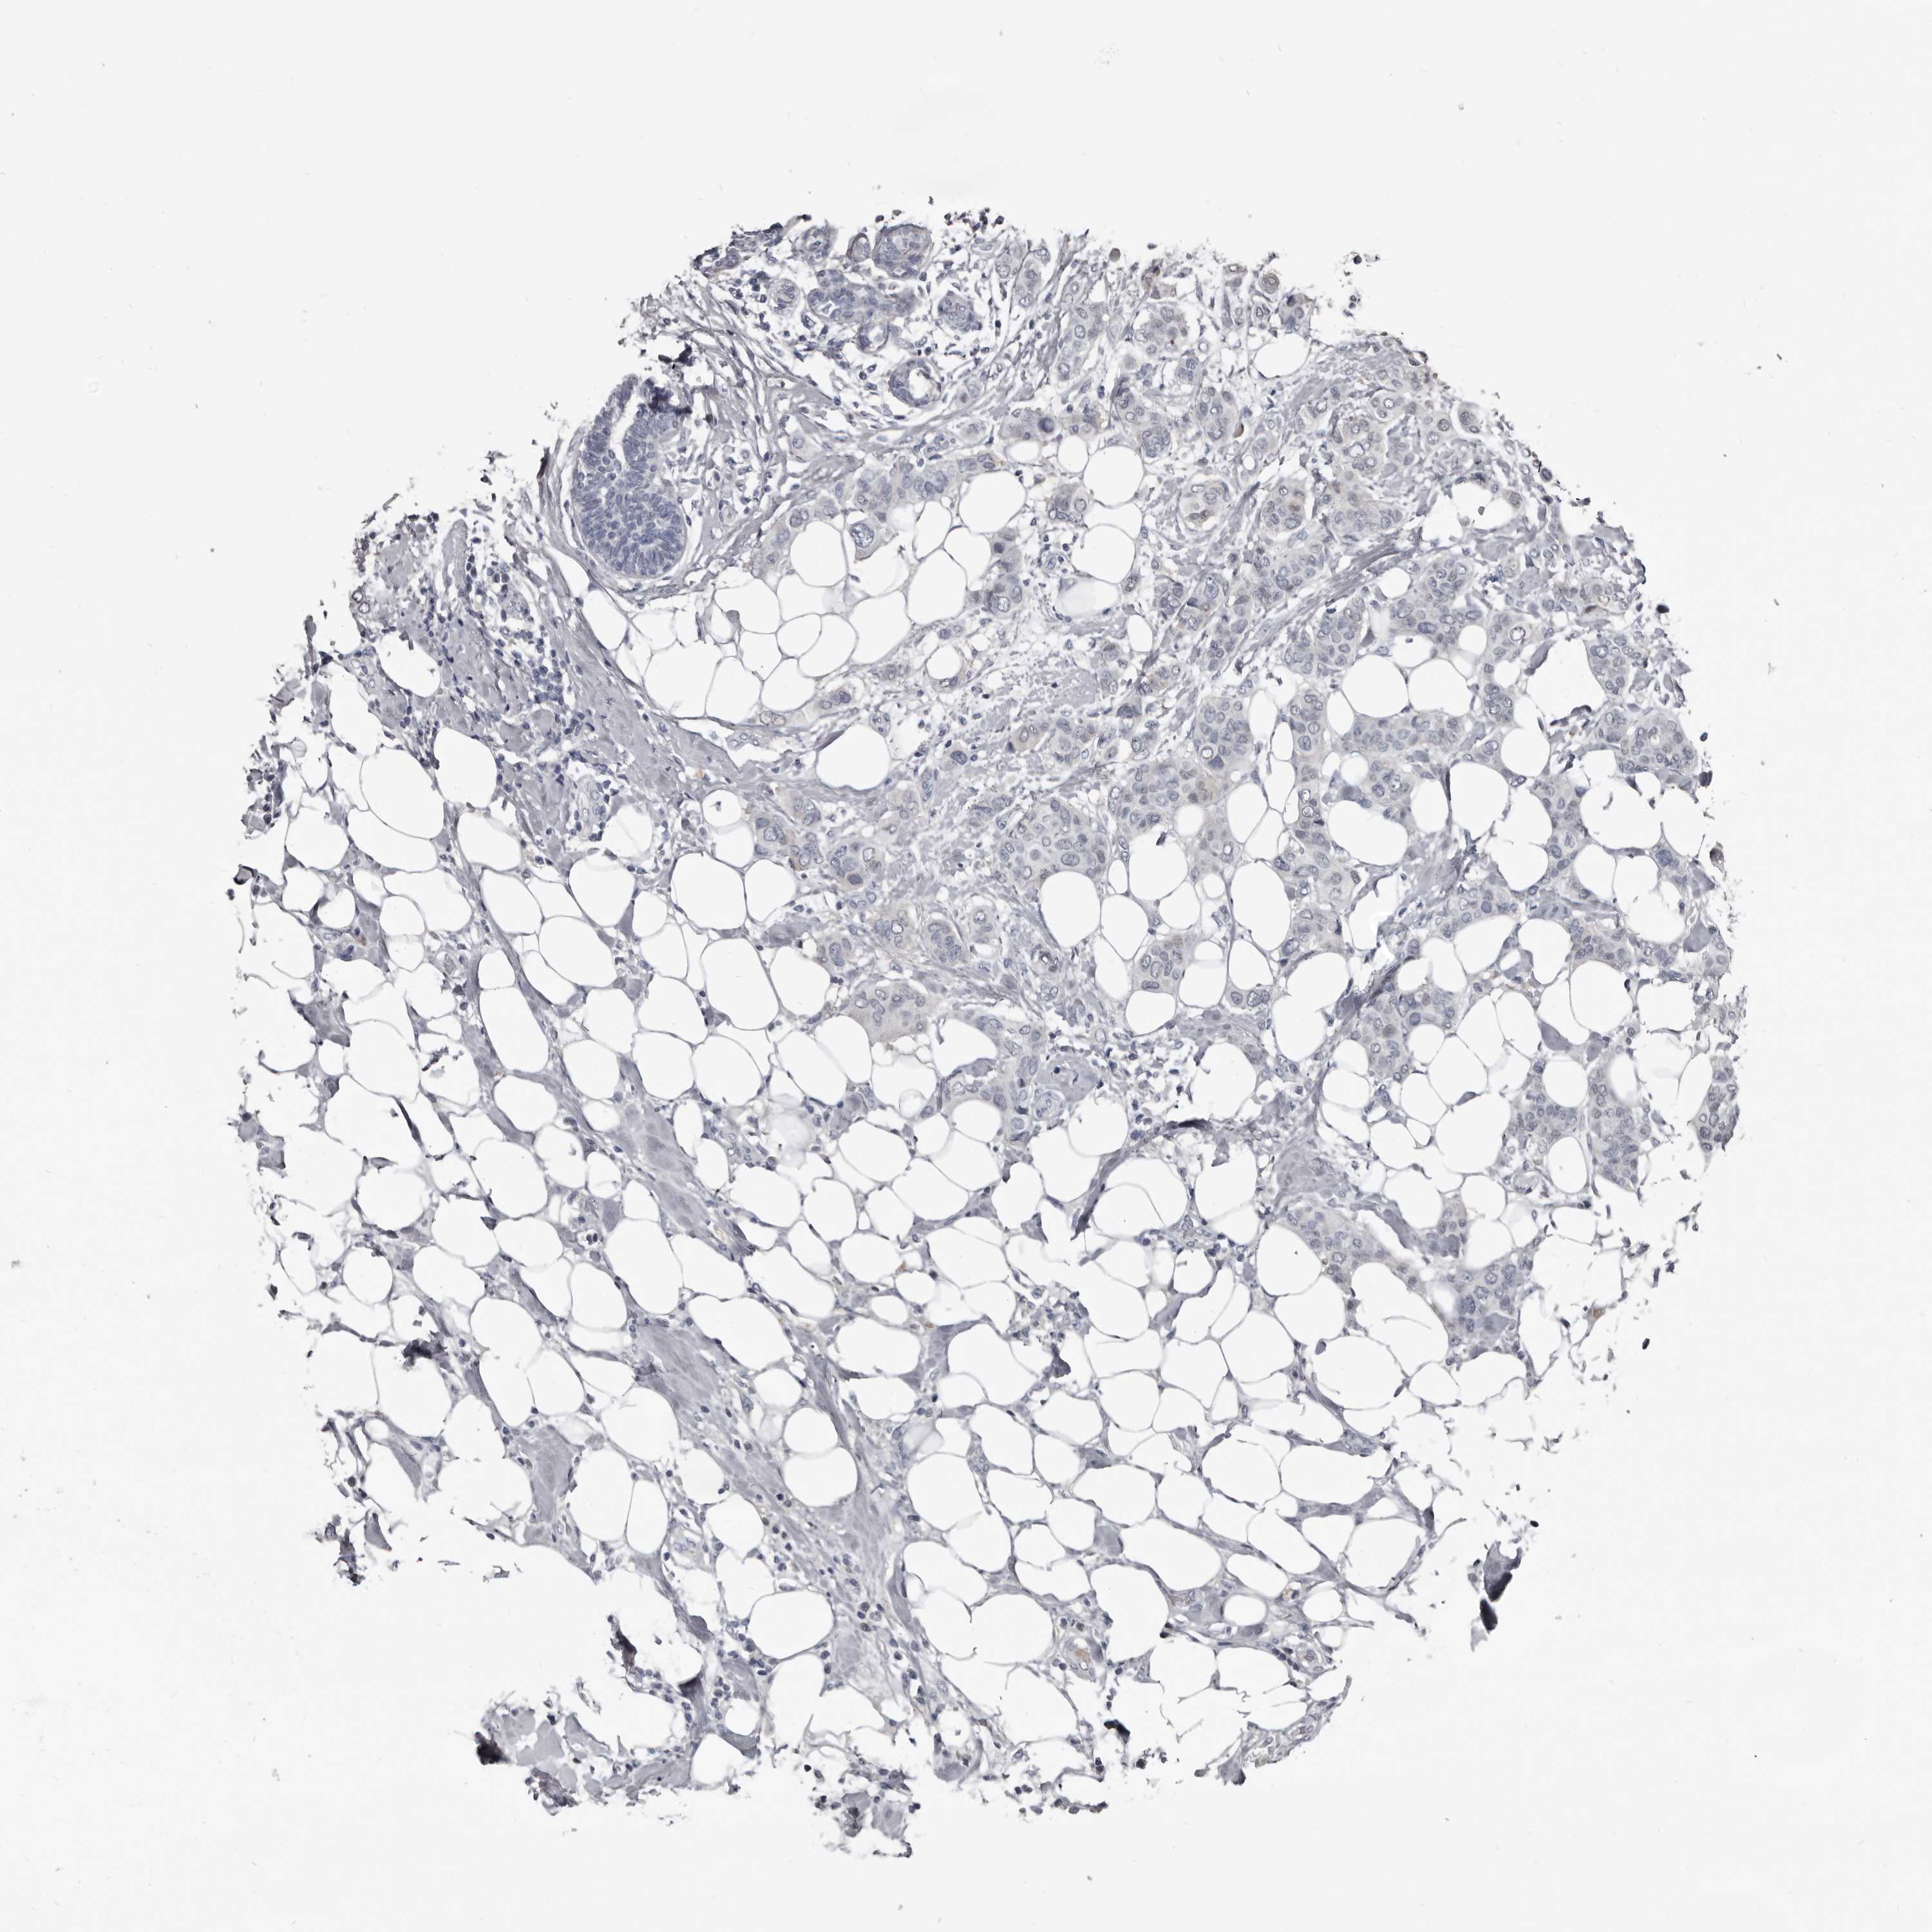

CANCER BREAST CANCER Show tissue menu

BRCA TCGA BRCA VALIDATION PROTEIN EXPRESSION

Breast cancer

Human cancer

Breast invasive carcinoma